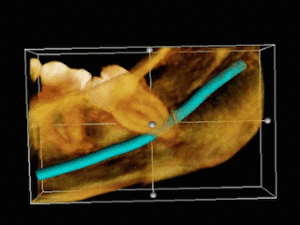

The upper left (picture right) and upper right (picture left) wisdom teeth are distoangularly impacted. The lower left wisdom tooth is horizontally impacted. The lower right wisdom tooth is vertically impacted (unidentifiable in orthopantomogram).